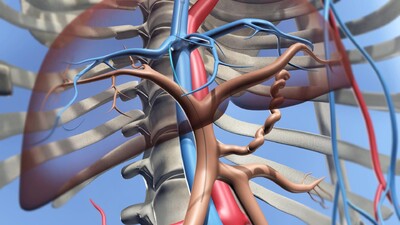

经颈静脉肝内门体静脉分流,静脉穿刺tipss

图片尺寸400x225